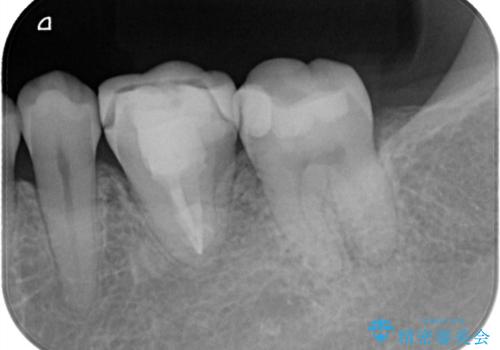

樋状根(といじょうこん)の根管治療